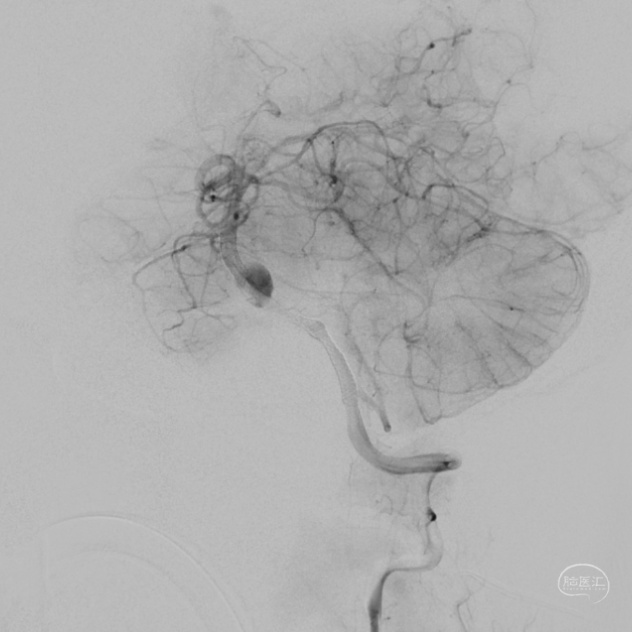

DSA:

3D重建显示基底动脉下部、双椎结合部、左椎多发夹层动脉瘤: